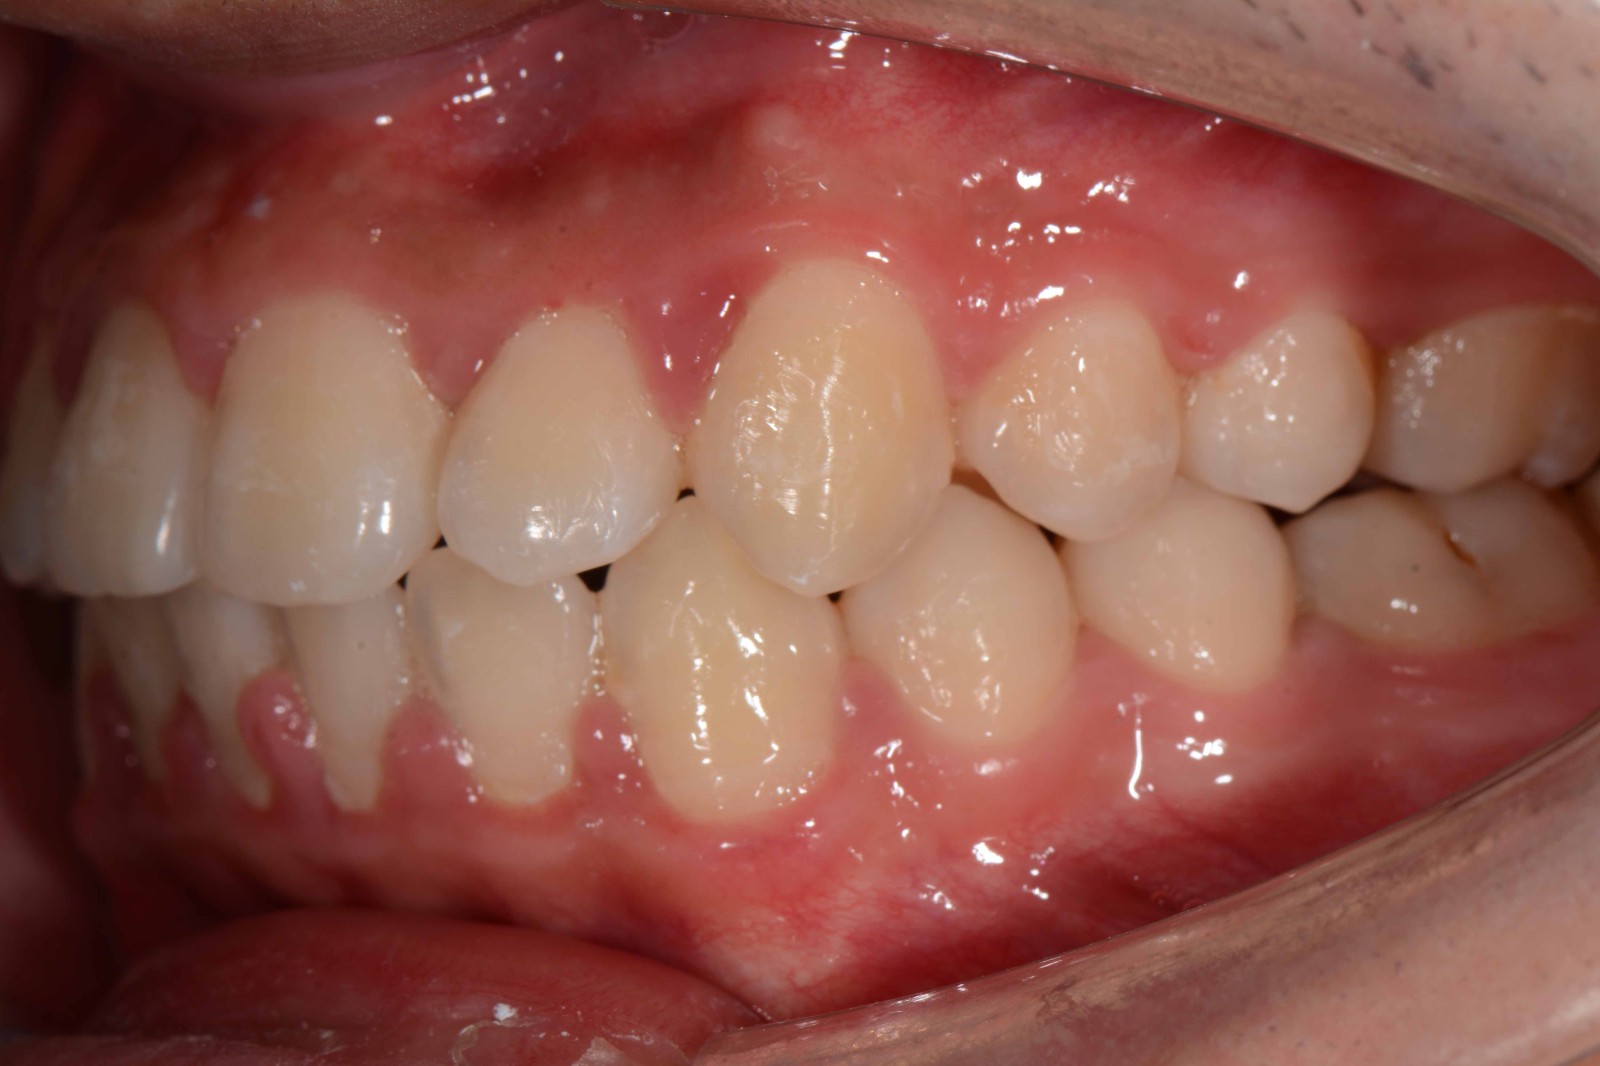

检查:拍摄口内面像照片,拍摄全景片侧位片,口扫,上下颌I-II度拥挤,中线不齐,局部反合,磨牙基本中性关系,上下前牙比较直立。

矫治后: